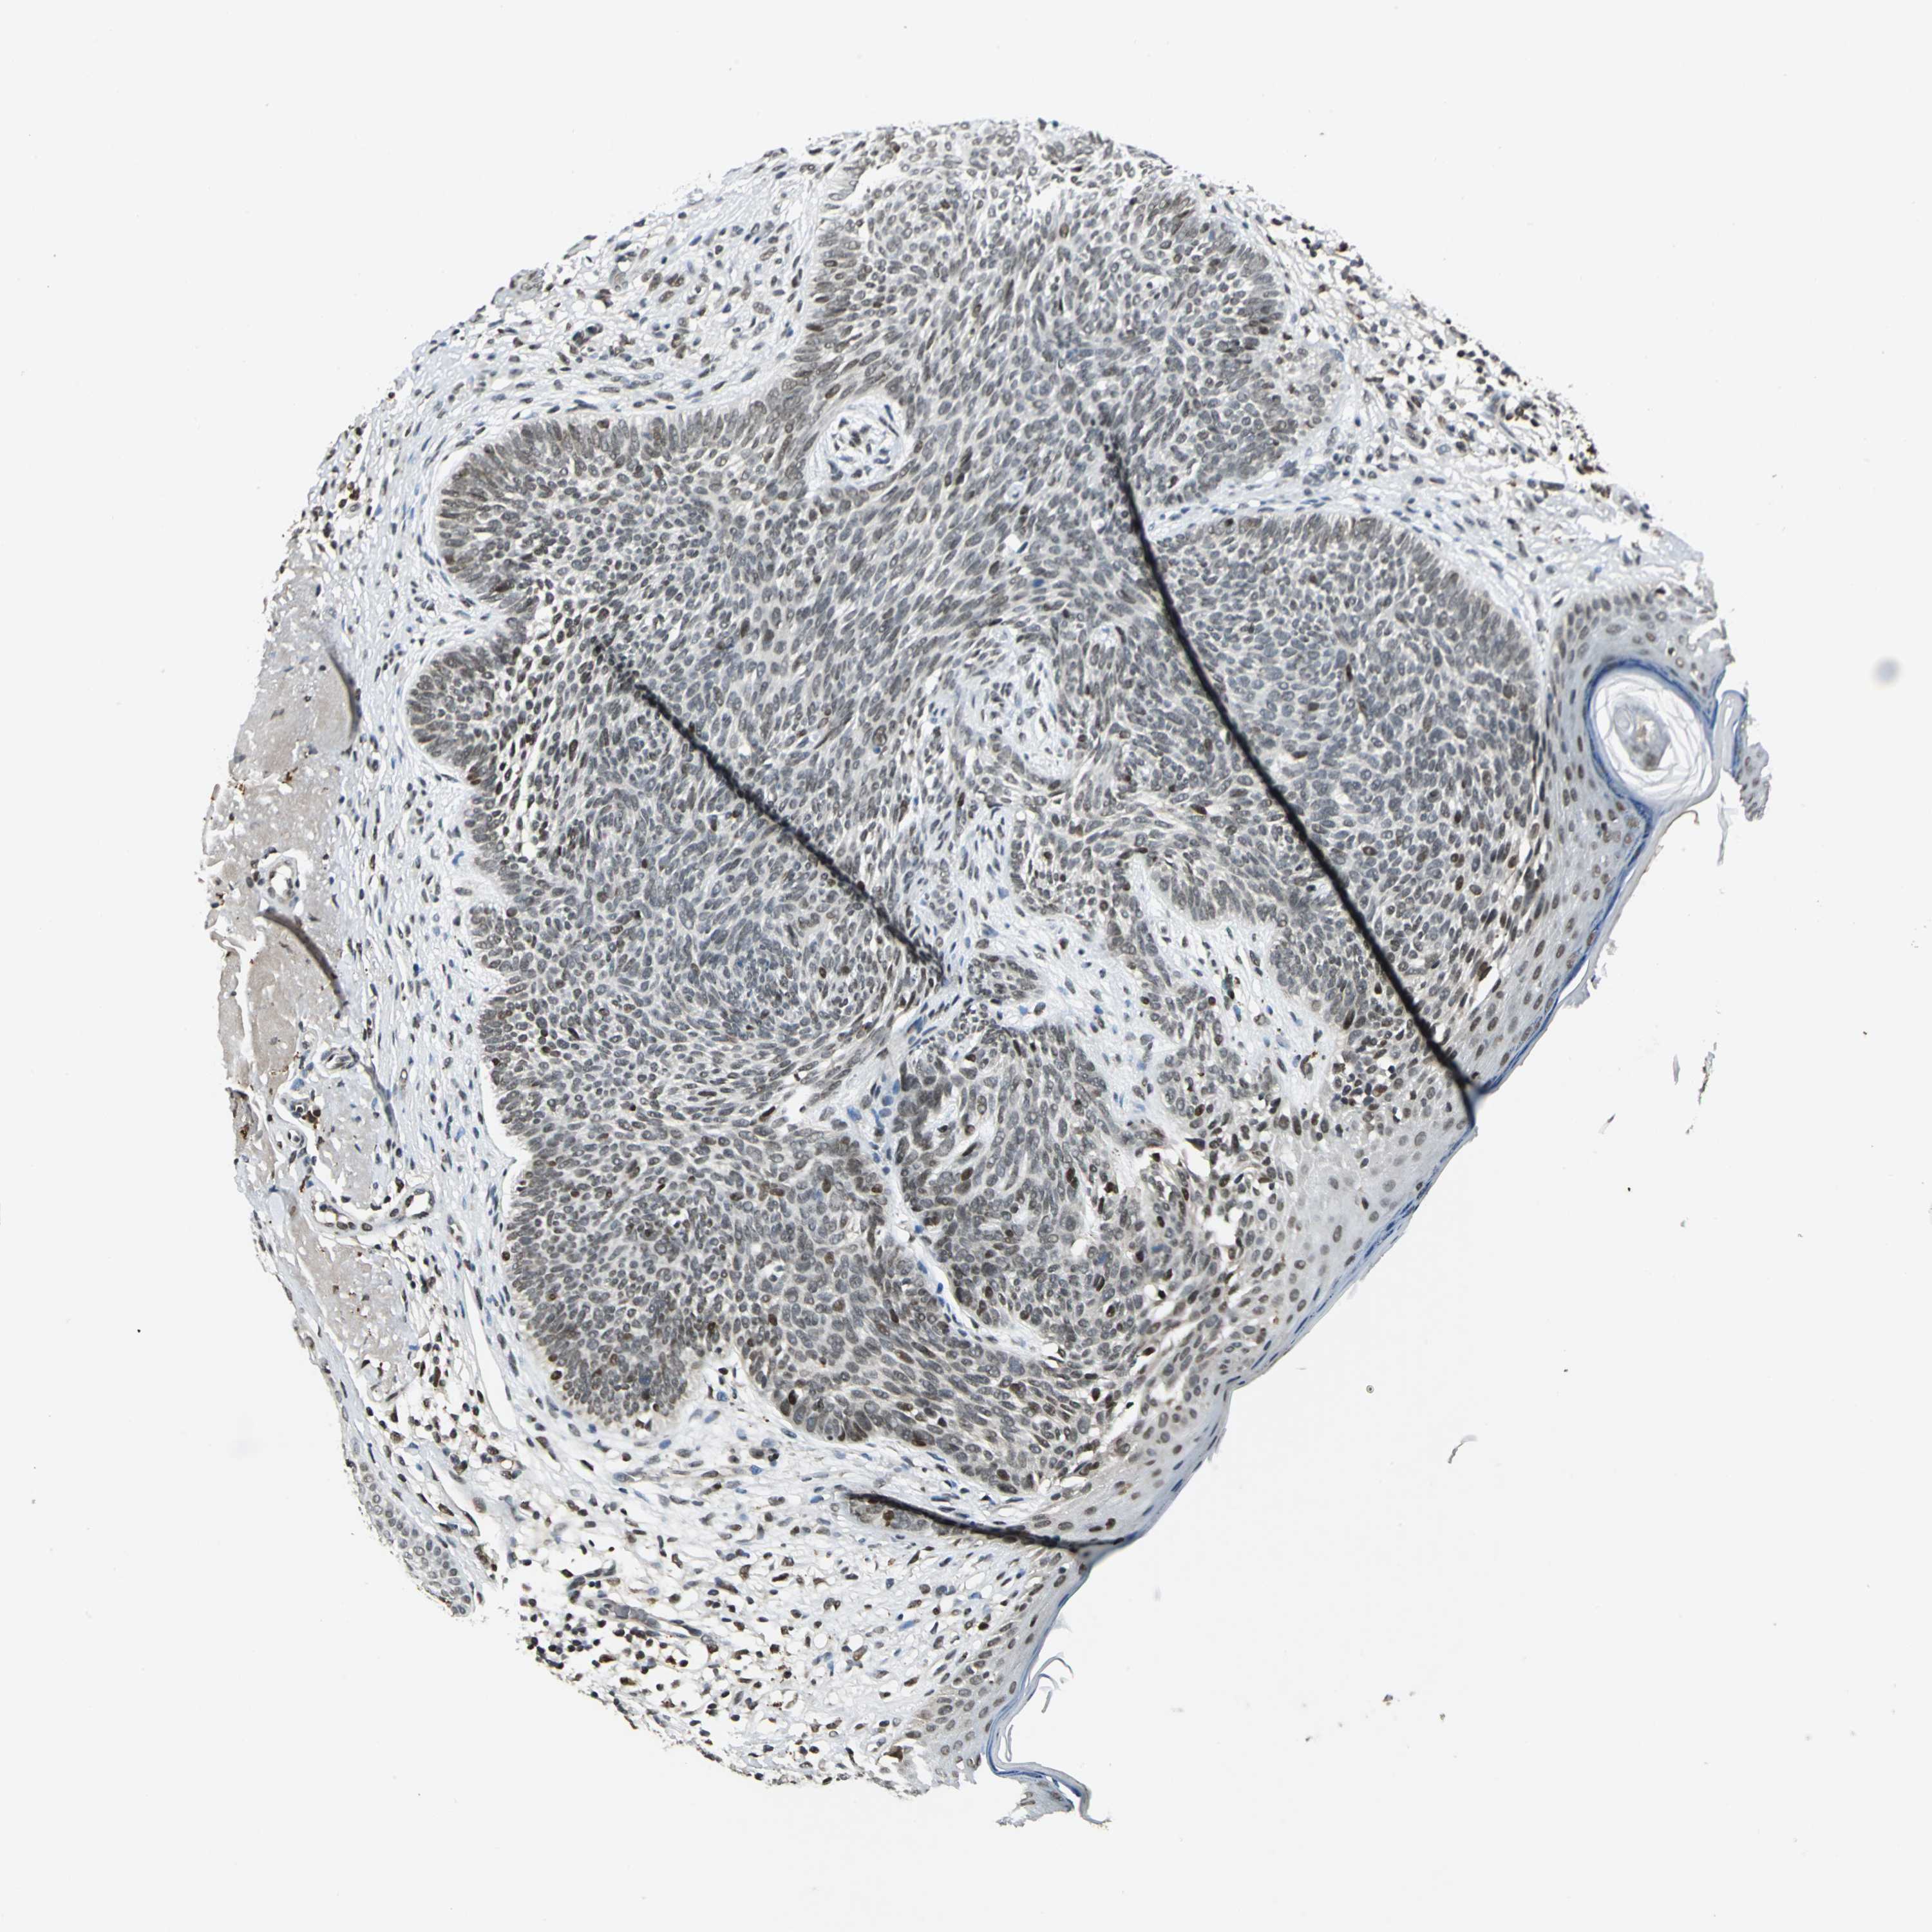

Basal cell and squamous cell cancer

SKIN CANCER - Protein expressioni

A mouse-over function shows sample information and annotation data. Click on an image to view it in a full screen mode. Samples can be filtered based on level of antibody staining by selecting one or several of the following categories: high, medium, low and not detected. The assay and annotation is described here.

Antibody stainingi

Antibody staining in the annotated cell types in the current human tissue is reported as not detected, low, medium, or high, based on conventional immunohistochemistry profiling in selected tissues. This score is based on the combination of the staining intensity and fraction of stained cells.

Each image is clickable and will lead to virtual microscopy that enables deeper exploration of all samples and also displays staining intensity scores, fraction scores and subcellular localization as well as patient and tissue information for each sample.

Antibody HPA005448

Staining

High

Intensity

Strong

Quantity

>75%

Location

Nuclear

Squamous cell carcinoma, NOS